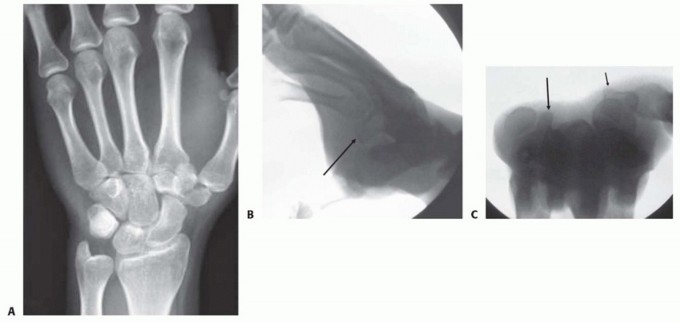

Imaging is the cornerstone of preoperative templating. Routine evaluation begins with high-quality posteroanterior, lateral, and oblique radiographs of the wrist. However, standard views are notoriously inadequate for isolating specific carpal pathology due to osseous overlap. Special radiographic projections are therefore essential. The carpal tunnel view is critical for evaluating the hamate hook and the trapezial ridge. The "papillon view"—a supinated oblique lateral projection with the wrist in radial deviation and the thumb abducted—is highly specific for profiling the hamate hook. Similarly, a 45-degree supinated lateral view optimally visualizes the pisotriquetral articulation.

Image

Despite optimal plain radiography, advanced imaging is frequently required. High-resolution computed tomography (CT) scanning with fine axial, coronal, and sagittal reconstructions has become the gold standard and the imaging modality of choice for complex carpal trauma. CT scans definitively confirm occult fractures, delineate intra-articular comminution, and reveal subtle associated injuries missed on plain films. They allow the surgeon to mentally construct a 3D model of the fracture, facilitating precise preoperative templating of screw trajectories and implant sizes. If dynamic instability is suspected but unconfirmed, an Examination Under Anesthesia (EUA) combined with real-time fluoroscopy (utilizing stress and distraction views) is performed immediately prior to the definitive procedure to finalize the surgical blueprint.